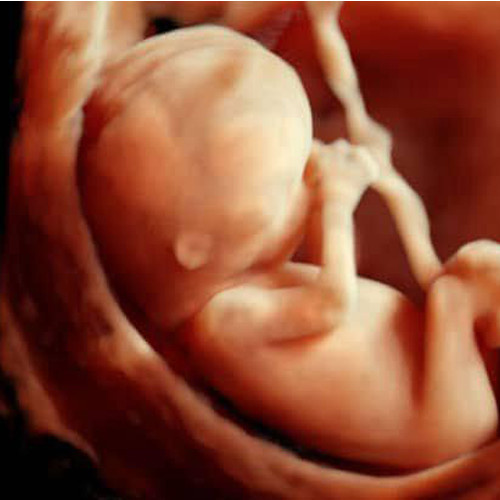

Best Scanning Center In Nakodar